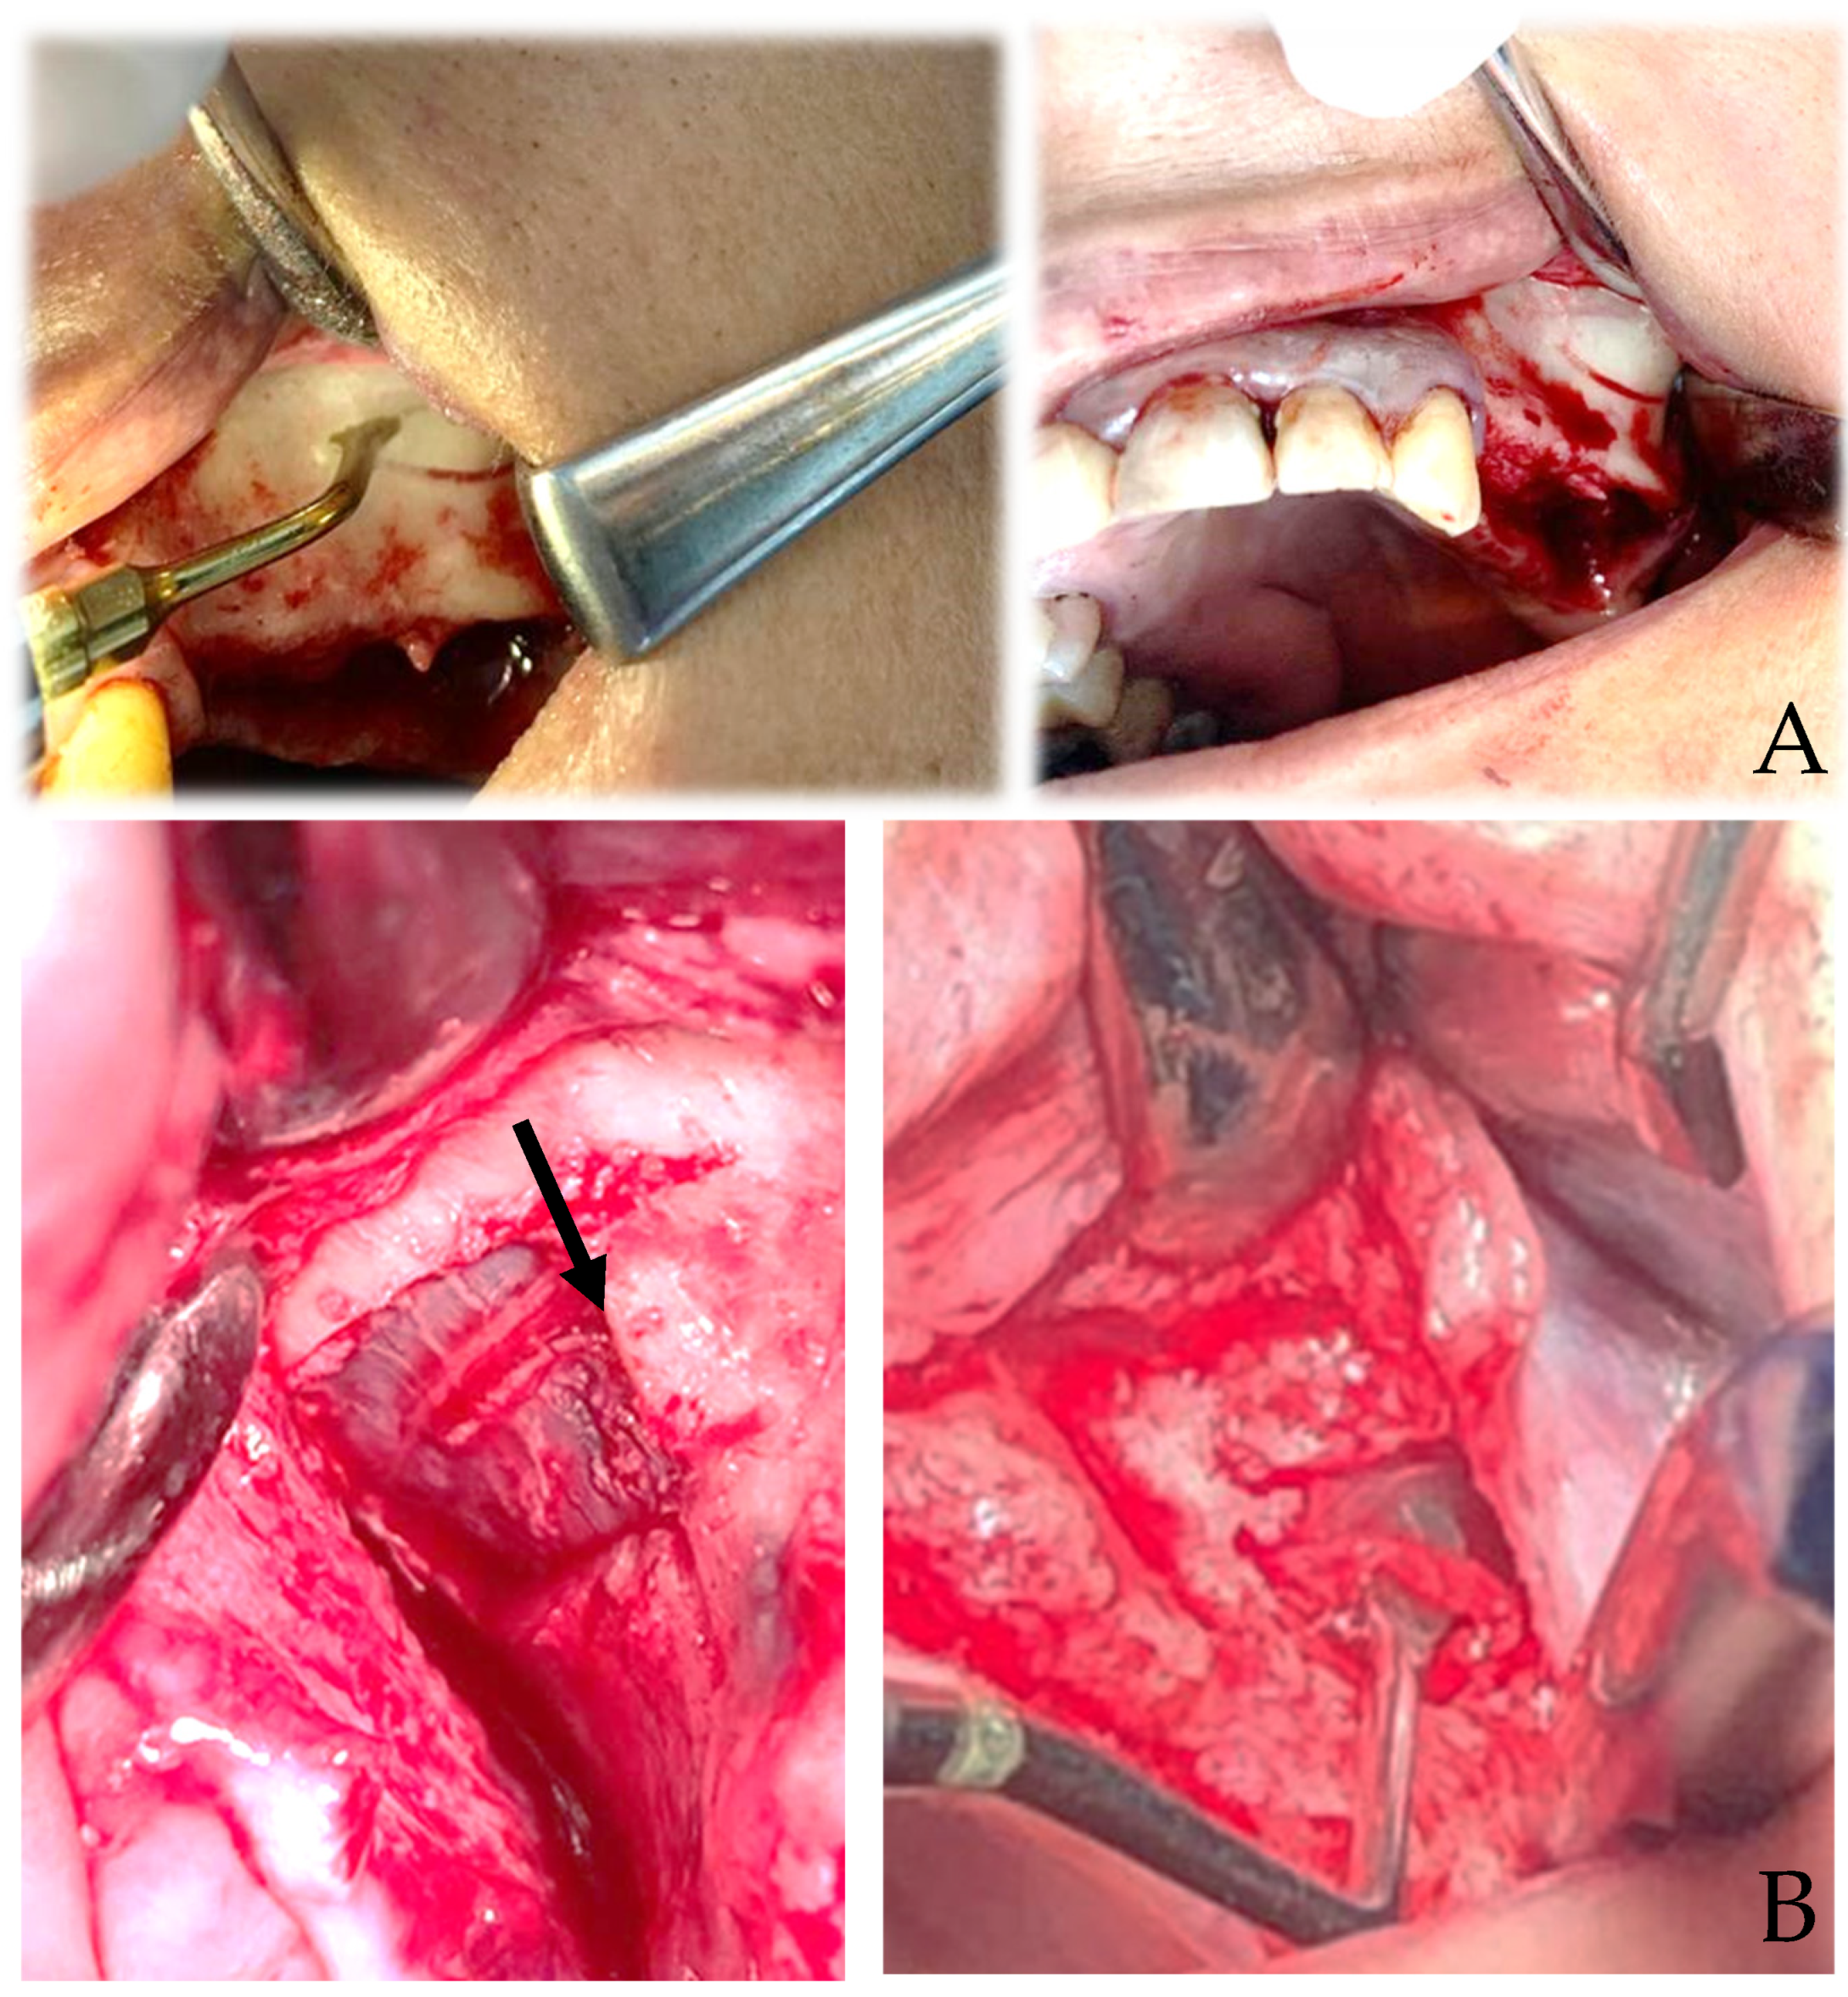

4.3. Surgical Techniques for Sinus Augmentation Using Platelet Derivatives